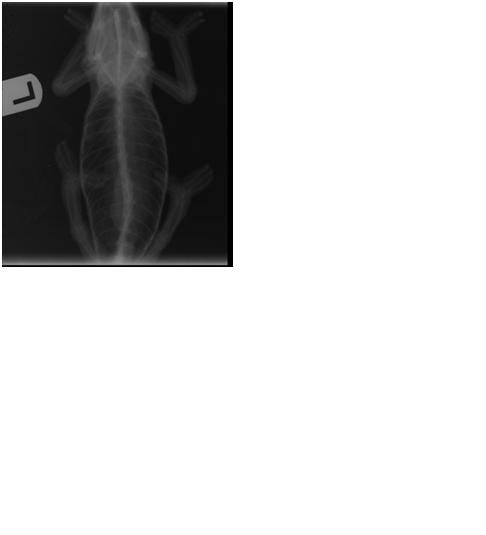

X-rays

X-ray with human fingers

X-rays

X-ray with human fingers